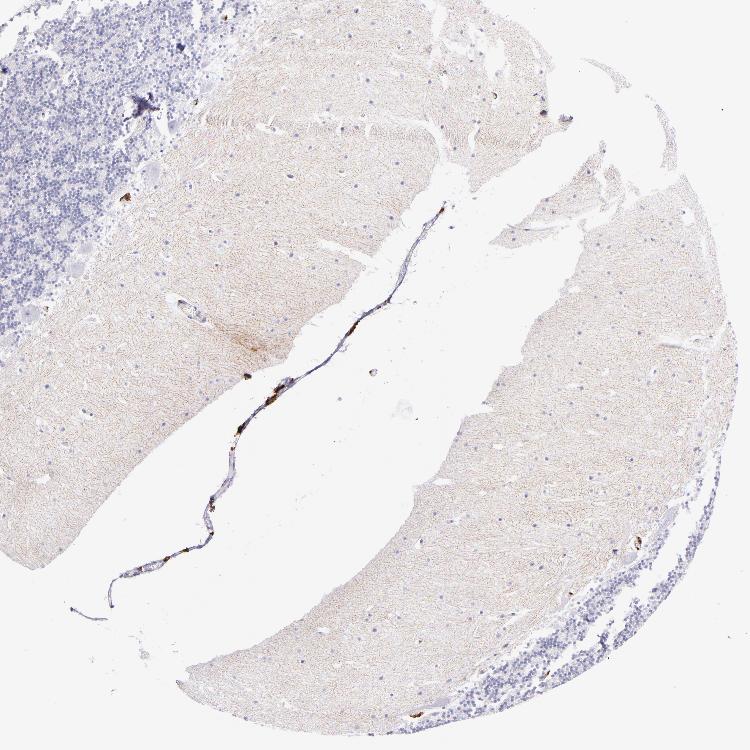

CEREBELLUM - Antibody stainingi

Antibody staining in the annotated cell types in the current human tissue is reported as not detected, low, medium, or high, based on conventional immunohistochemistry profiling in selected tissues. This score is based on the combination of the staining intensity and fraction of stained cells.

Each image is clickable and will lead to virtual microscopy that enables deeper exploration of all samples and also displays staining intensity scores, fraction scores and subcellular localization as well as patient and tissue information for each sample.

Antibody HPA046404Antibody HPA051974Antibody CAB002432

Purkinje cells LowNot detectedNot detected

Cells in granular layer Not detectedNot detectedNot detected

Cells in molecular layer Not detectedNot detectedNot detected